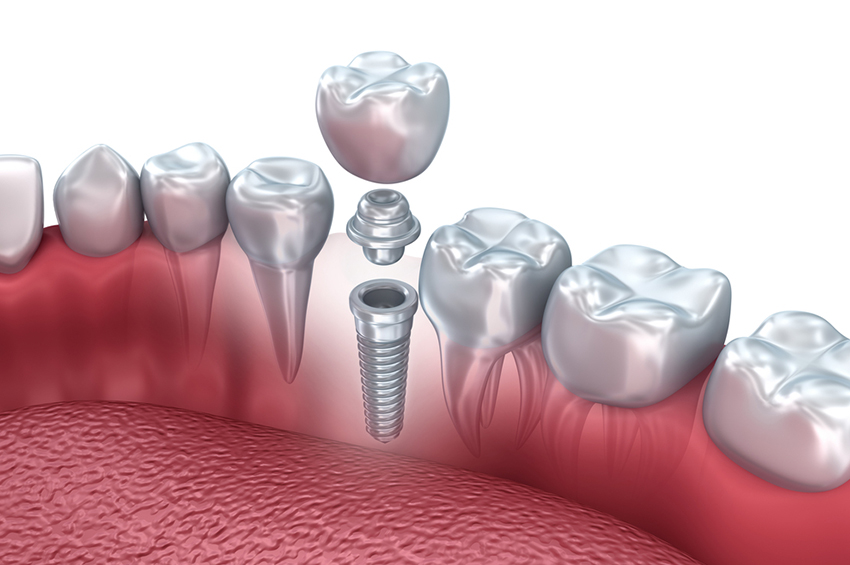

Dental Implants

Dental implants are a revolutionary solution for replacing missing teeth, consisting of small titanium posts that are surgically inserted into the jawbone. These posts act as artificial roots, providing a stable foundation for attaching replacement teeth, such as crowns or bridges. Unlike dentures, which are removable, dental implants offer a permanent solution that mimics the look and function of natural teeth. If you’re looking for dental implants in Yerawada, finding a trusted dental clinic is essential for high-quality care and long-lasting results.

Dental implants come in various types, primarily categorized based on their placement and design:

The process of getting dental implants typically involves several steps: